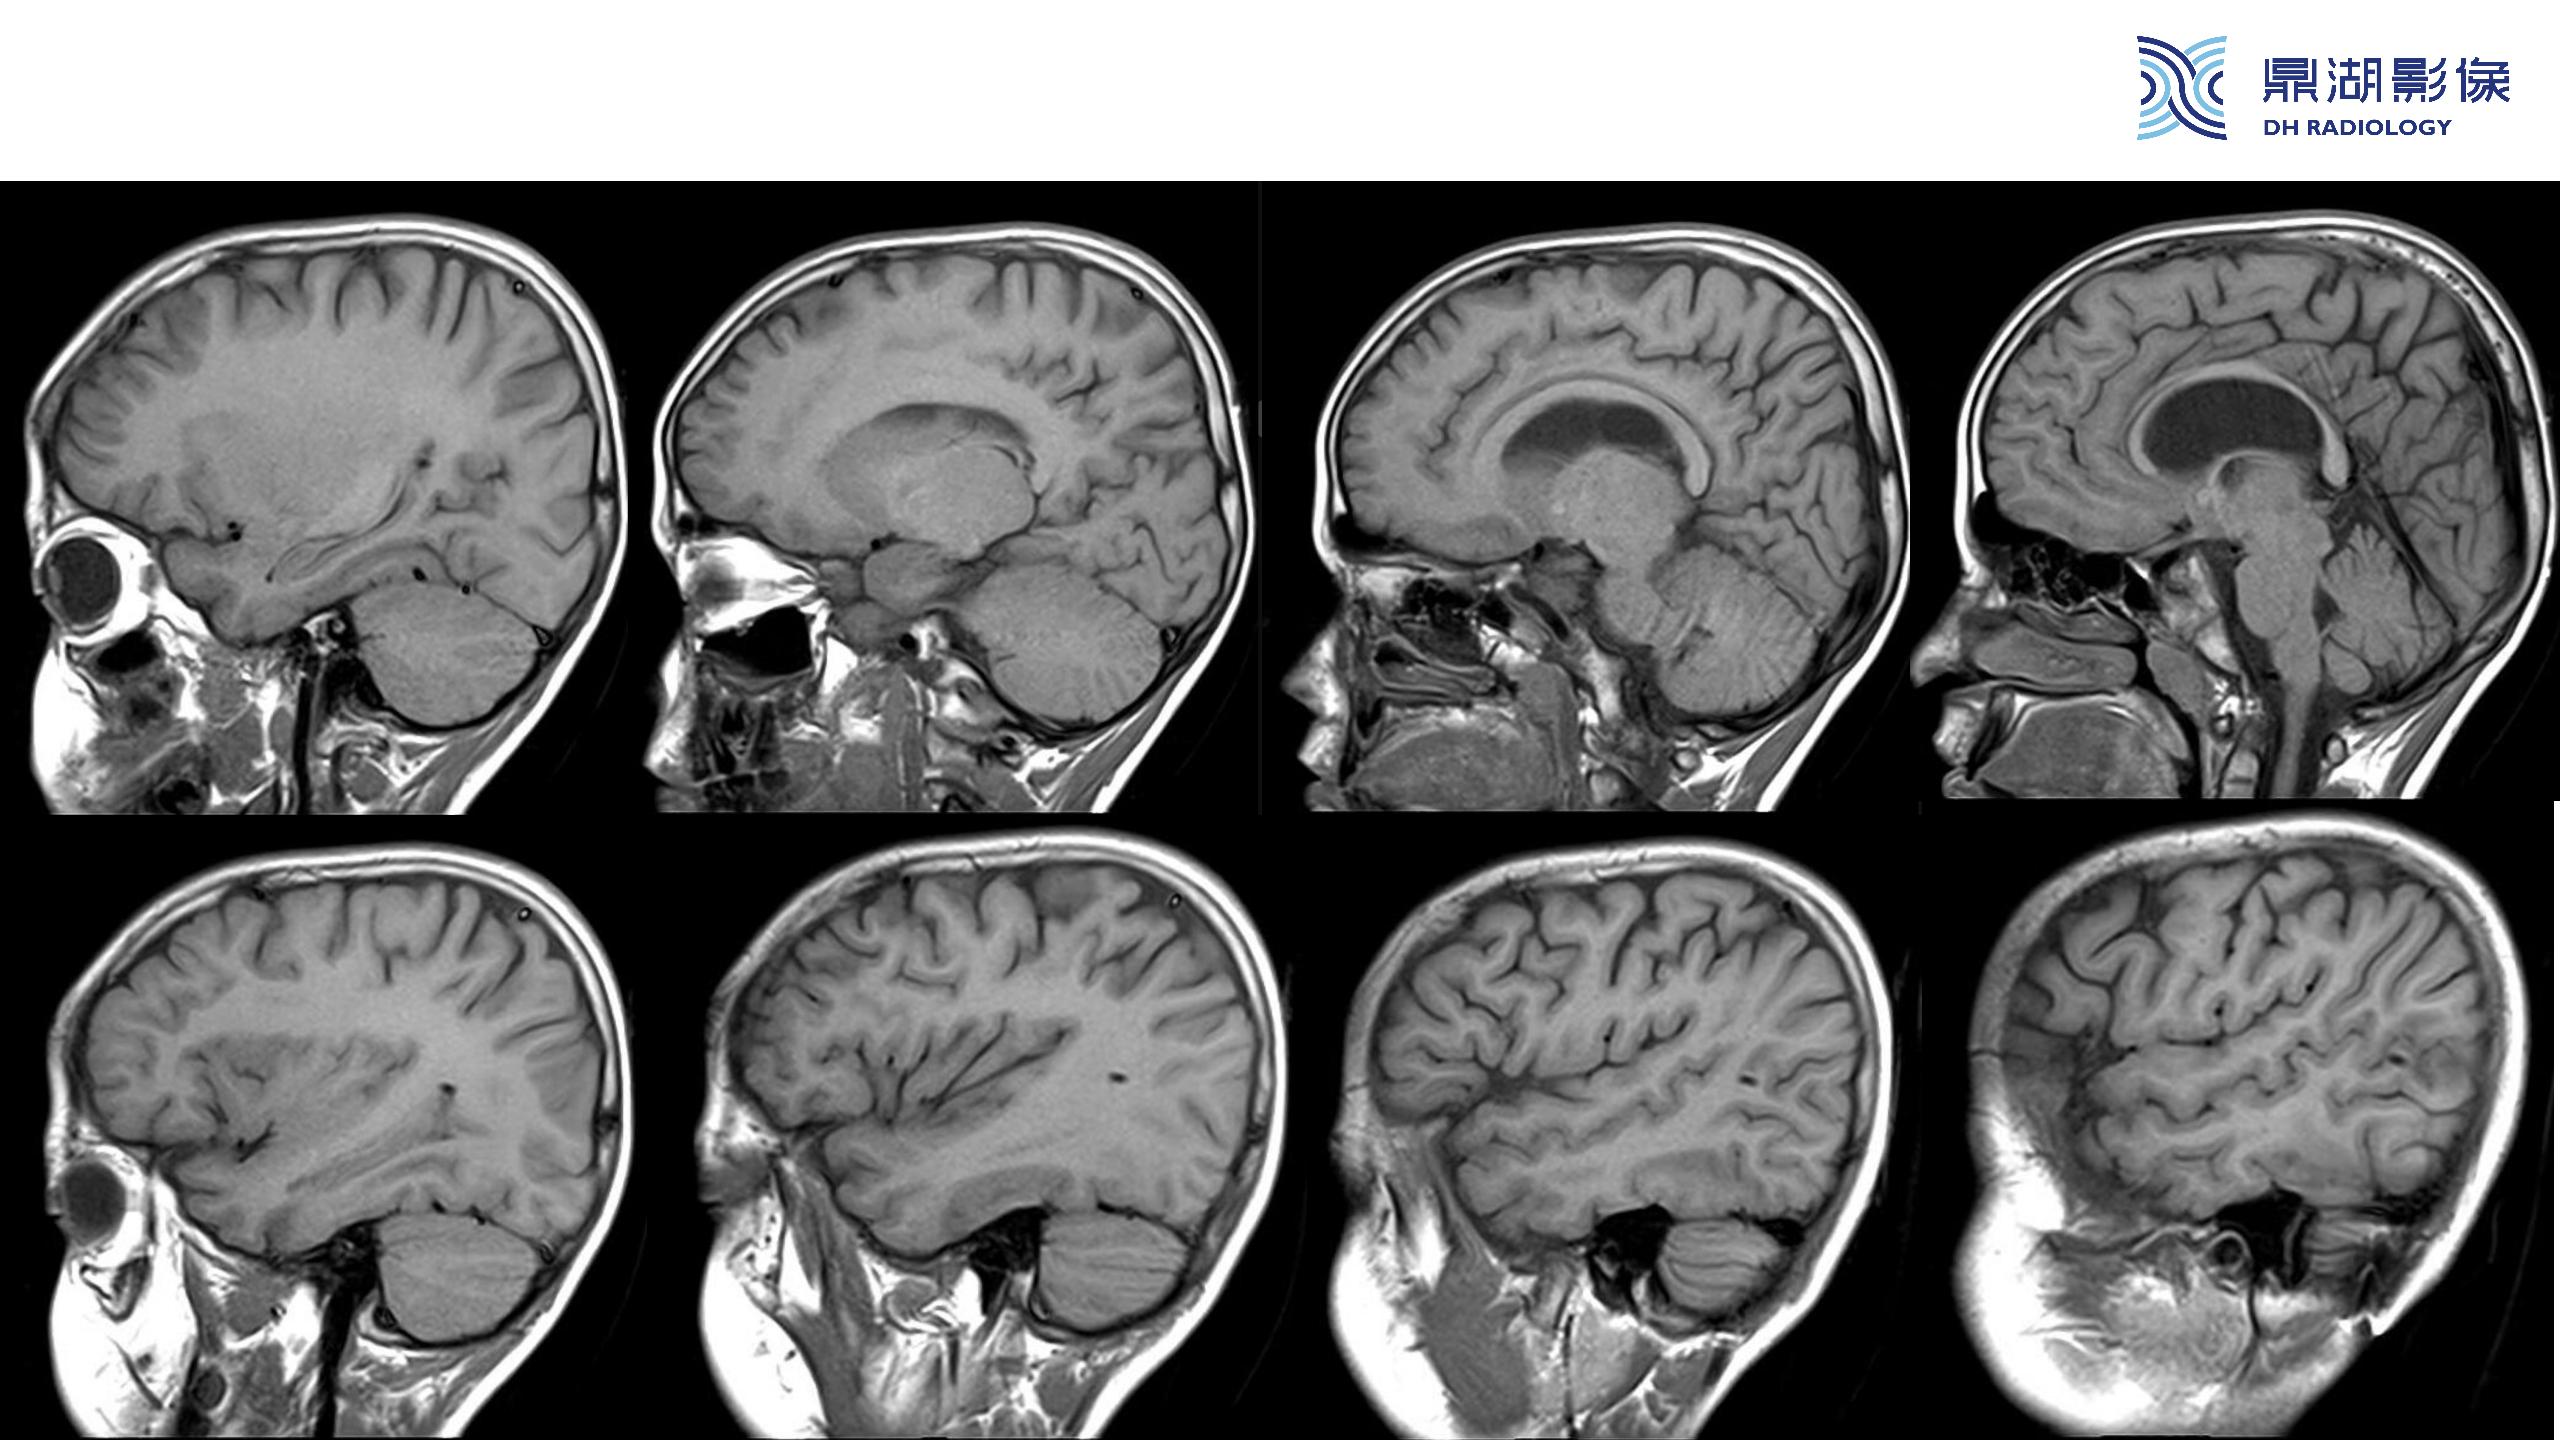

裂隙脑室综合征 (slit ventricle syndrome,SVS)-鼎湖社群读片病例